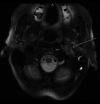

Case report: An 83-year-old woman presented with worsening episodes of dizziness of a few months duration. She also complained of tinnitus and hearing loss, more severe on the left side. Examination revealed a red bulging left-sided tympanic membrane, conductive hearing loss, and a bruit at the base of the skull. Dix-Hallpike test was negative. CT head and MRI brain revealed findings consistent with a large left-sided jugulotympanic paraganglioma, which was found to be hormonally inactive on laboratory tests. The patient underwent treatment with radiotherapy, which resulted in partial improvement of symptoms.

Conclusions: Jugulotympanic paraganglioma may manifest in the elderly with the chief complaint of intermittent vertigo, as in our case. A red bulging mass on otoscopy raises the suspicion, necessitating further investigations, including CT and MRI.